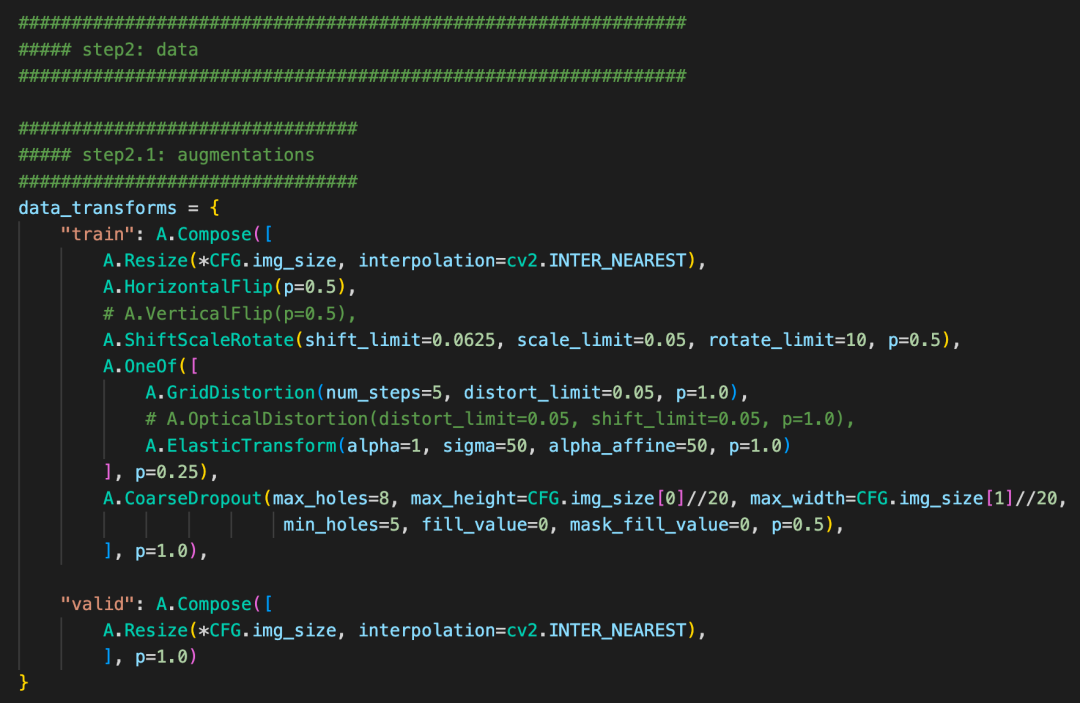

4、baseline

本次提供的baseline分为hypre-parameter, data, model, Loss, train五个方面。

数据增强:多分辨率训练、elastictransformer等